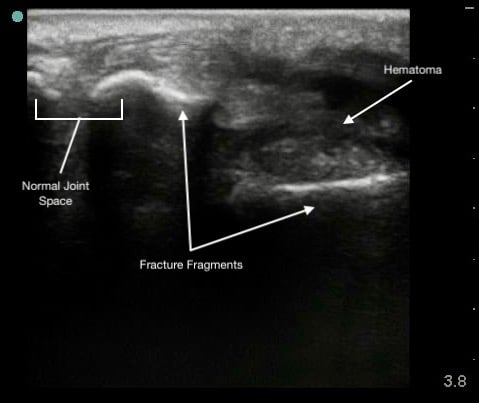

Shoulder Dislocation

Anterior Dislocation:

- The humeral head is displaced anterior to the glenoid.

- Appears at the bottom of the screen as the transducer is placed on the posterior shoulder.

- Movement is away from the transducer since the orientation is posterior-to-anterior.

Figure 9.

Anterior shoulder dislocation with overlying hematoma

Hypoechoic hematoma or effusion may be visible in the surrounding soft tissue.